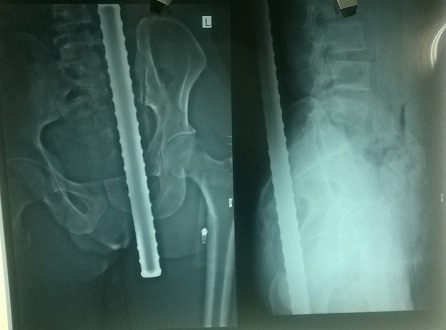

Bé gái bị tai nạn giao thông được các bác sĩ nỗ lực giành giật lại sự sống. Ảnh: